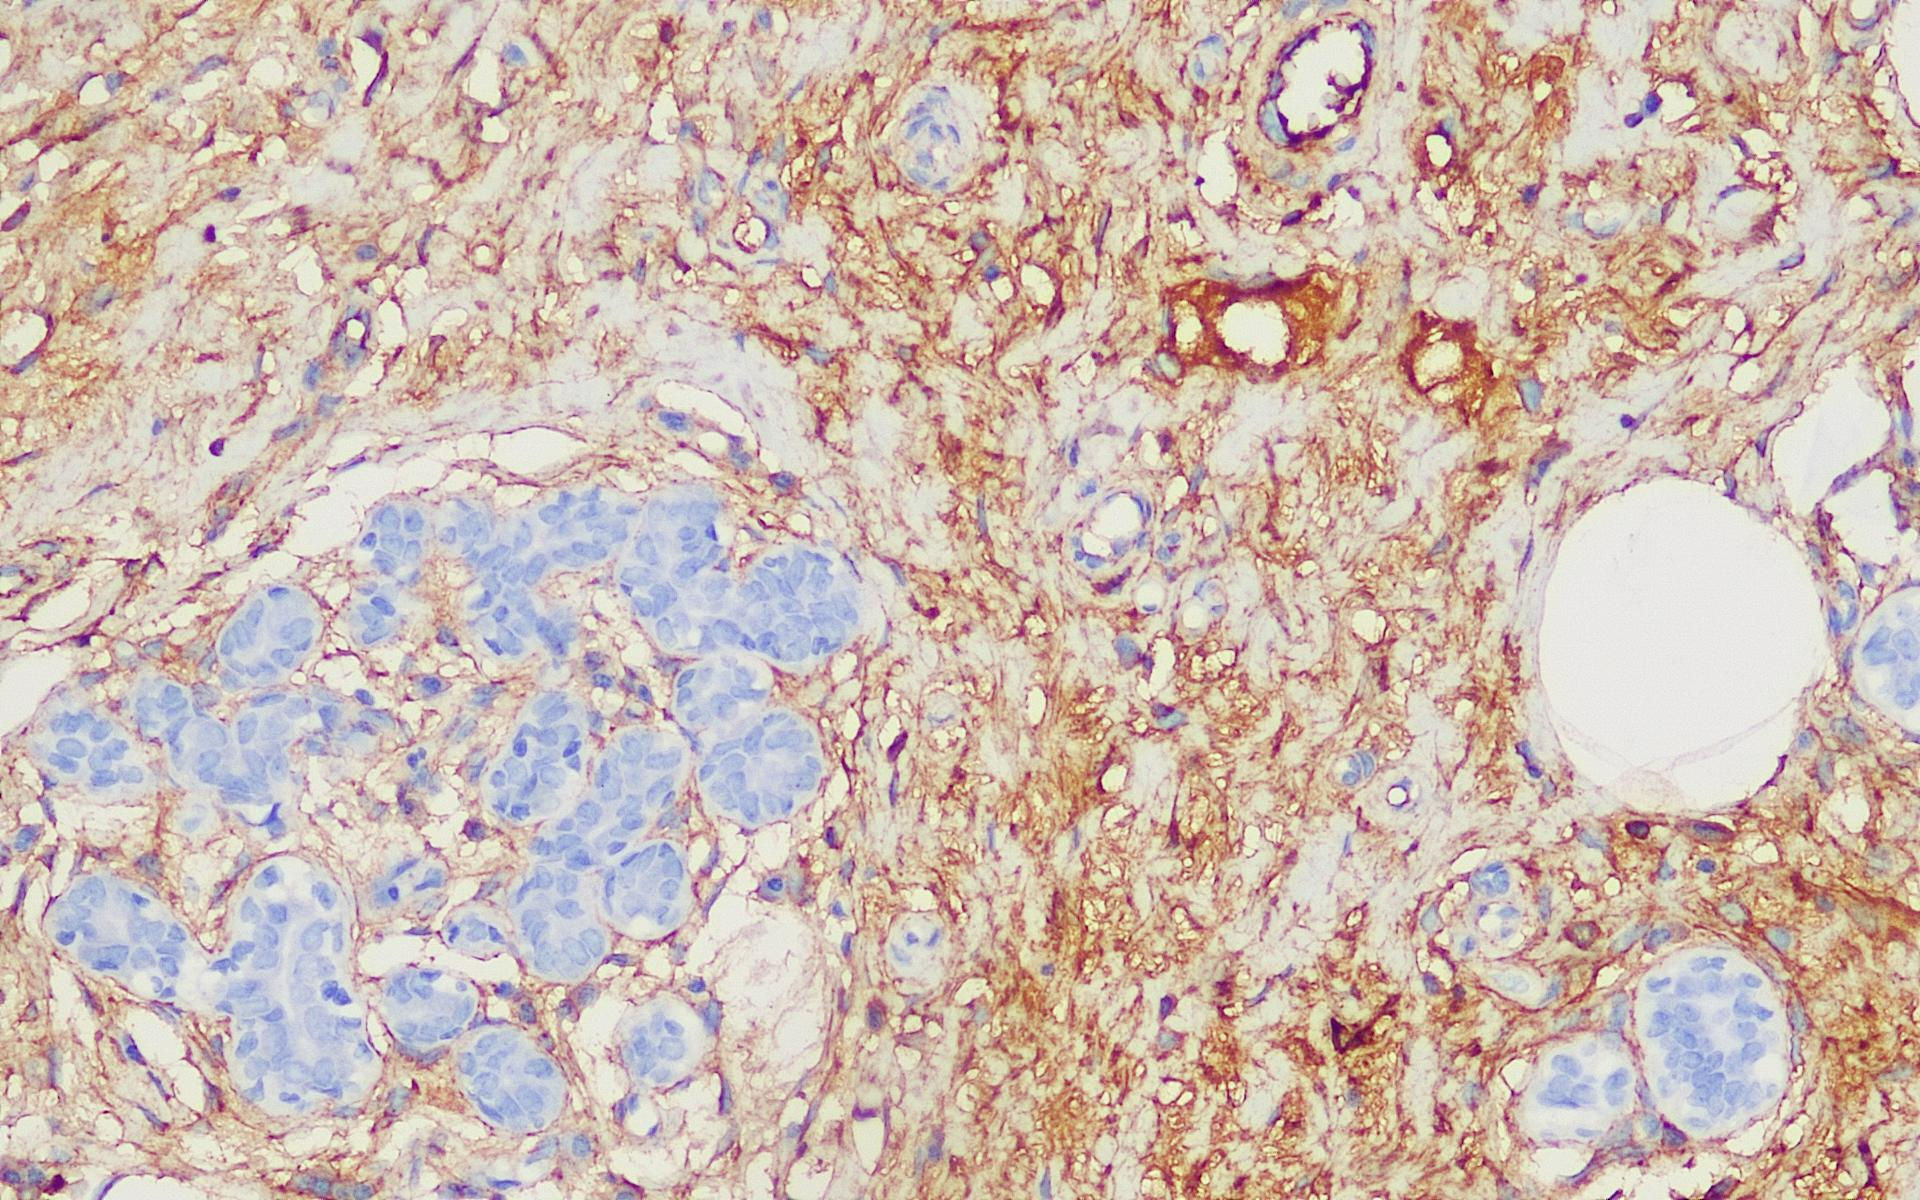

Fibronectin抗体试剂

阳性对照:乳腺癌

Fibronectin抗体试剂可与Fibronectin分子抗原特异性结合,含Fibronectin抗体试剂的免疫组化试剂盒适用于恶性上皮肿瘤的浸润和预后判断。